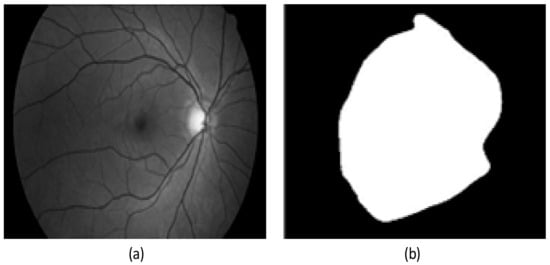

2.1. Preprocessing Based on Histogram

2.2. Preprocessing Based on Adaptive Thresholding